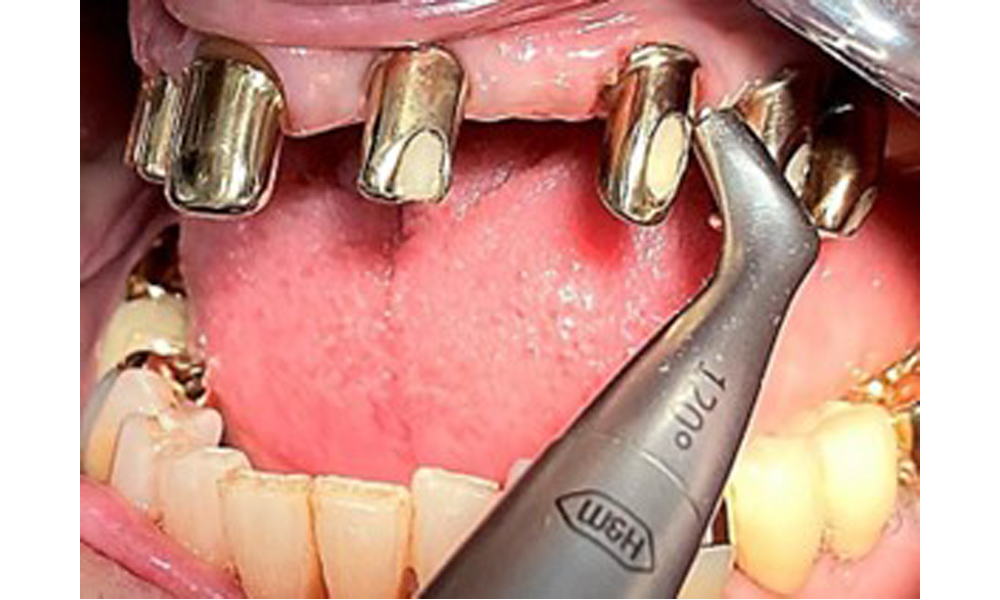

На пациентката е поставена комбинирана подвижна горночелюстна телескопична протеза преди повече от 25 години (фиг. 1, фиг. 2, фиг. 3) и тя е много доволна от протезите си. Пациентката има адекватна фиксирана протеза за долната челюст (фиг. 4).

Денталните открития са следните: Комбинирани снемаеми протези на импланти и телескопични протези, поддържани от зъби, на импланти 15, 13, 21, 23, 24, 25 и зъб 11 (фиг. 1, фиг. 2, фиг. 3). Пациентът е снабден с фиксирана долночелюстна протеза. Над зъби 37-34 и 45-47 бяха налични адекватни мостове (фиг. 4), краищата на коронките бяха интактни и нямаше активен кариес. Върху зъб 43 имаше композитна пломба с маргинална празнина. Имаше рецесия на долната гингива, която разкриваше от 1 до 3 mm от кореновата повърхност. Това се отнася и за 11.

За отстраняване на зъбния камък и конкрементите по естествените зъби могат да се използват звукови/ултразвукови или конвенционални ръчни инструменти (8). За отстраняване на минерализираната плака от имплантите трябва да се използват титаниеви или пластмасови кюрети (фиг. 10), или пластмасова, или PEEK приставка (фиг. 11) по време на ултразвуковото лечение, за да се избегне увреждане на повърхностите на имплантите.